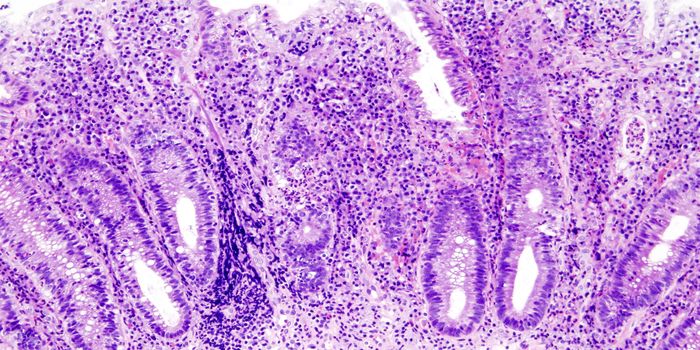

MAR 26, 2018Cannabis SciencesPilot trial results published using CBD-rich extract to evaluate its effects on Ulcerative Colitis using randomized, dou ...